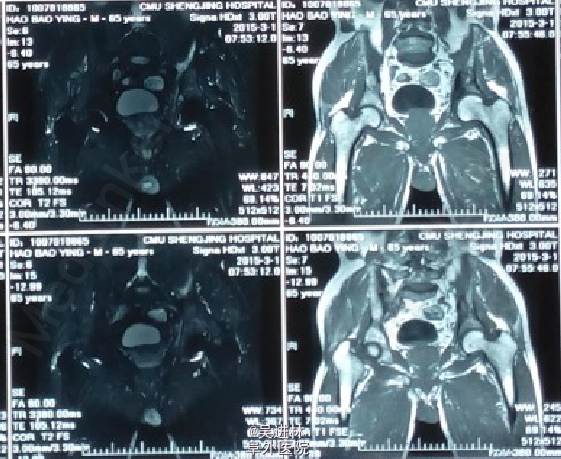

患者老年男性,主因“左髋部疼痛不适2年余”入院;查体:左侧腹股沟压痛+;活动度受限;4字试验+,托马斯征+;辅助检查:CT示左侧髋臼骨多发骨质破坏,累及周围软组织;全身骨显像示左髋臼窝核素浓聚灶;MIR描述如图。T-spot阳性!现在对于诊断基本持两种意见:因为患者病灶累及软组织,MRI上髂腰肌可见高信号,而且T-spot阳性,考虑TB。另外一种观点认为:病人除了T-spot并无其他TB征象,而且如果是TB的话,现在早就应该形成冷脓肿和窦道了,再者从MRI上来看,病灶呈膨胀性生长,边界清楚,所以考虑骨肿瘤可能性。what do you think?